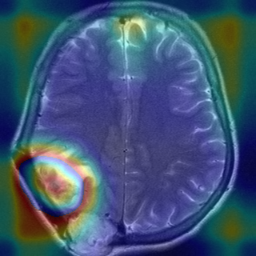

Figure 1: Heatmap Comparison of Unhealthy Images. Different columns show unhealthy MRI images of different positions, sizes, and textures. The first row is the raw image. The second row is the heatmap predicted with PatchCore. The third raw is the heatmap predicted with the proposed method.